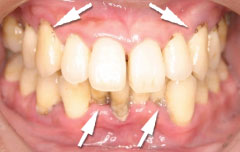

| 歯茎にプラーク(歯垢着が)と歯石の沈認められます。歯肉が腫れ、出血がありました。 | 歯科衛生士の治療と、ブラッシング技術の向上により、歯茎が引き締まり健康的な状態になりました。 | |

| 切除療法の目的は、しっかりと虫歯を取り除き、健全な歯質の獲得と生理的骨形態を付与することす。治療後の歯肉も、高い清掃性、長期安定性を兼ね揃え、永続性が期待できます。(一方で、歯の形態が長くなる・治癒に時間がかかりますので、切除療法と組織付着療法の術式選択は、患者様とのお話合いの上で決めて行きます。) | |||